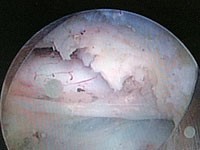

腰椎椎間板ヘルニアに対する経皮的内視鏡下椎間板摘出術(PELD)

平成20年に導入したPELDは、低侵襲(6ミリメートルの創)かつ短い入院期間と高い治療効果が特徴です。

PELD

PELD(経皮的内視鏡下椎間板摘出術)の様子1

PELD(経皮的内視鏡下椎間板摘出術)の様子2

PELD(経皮的内視鏡下椎間板摘出術)の様子3